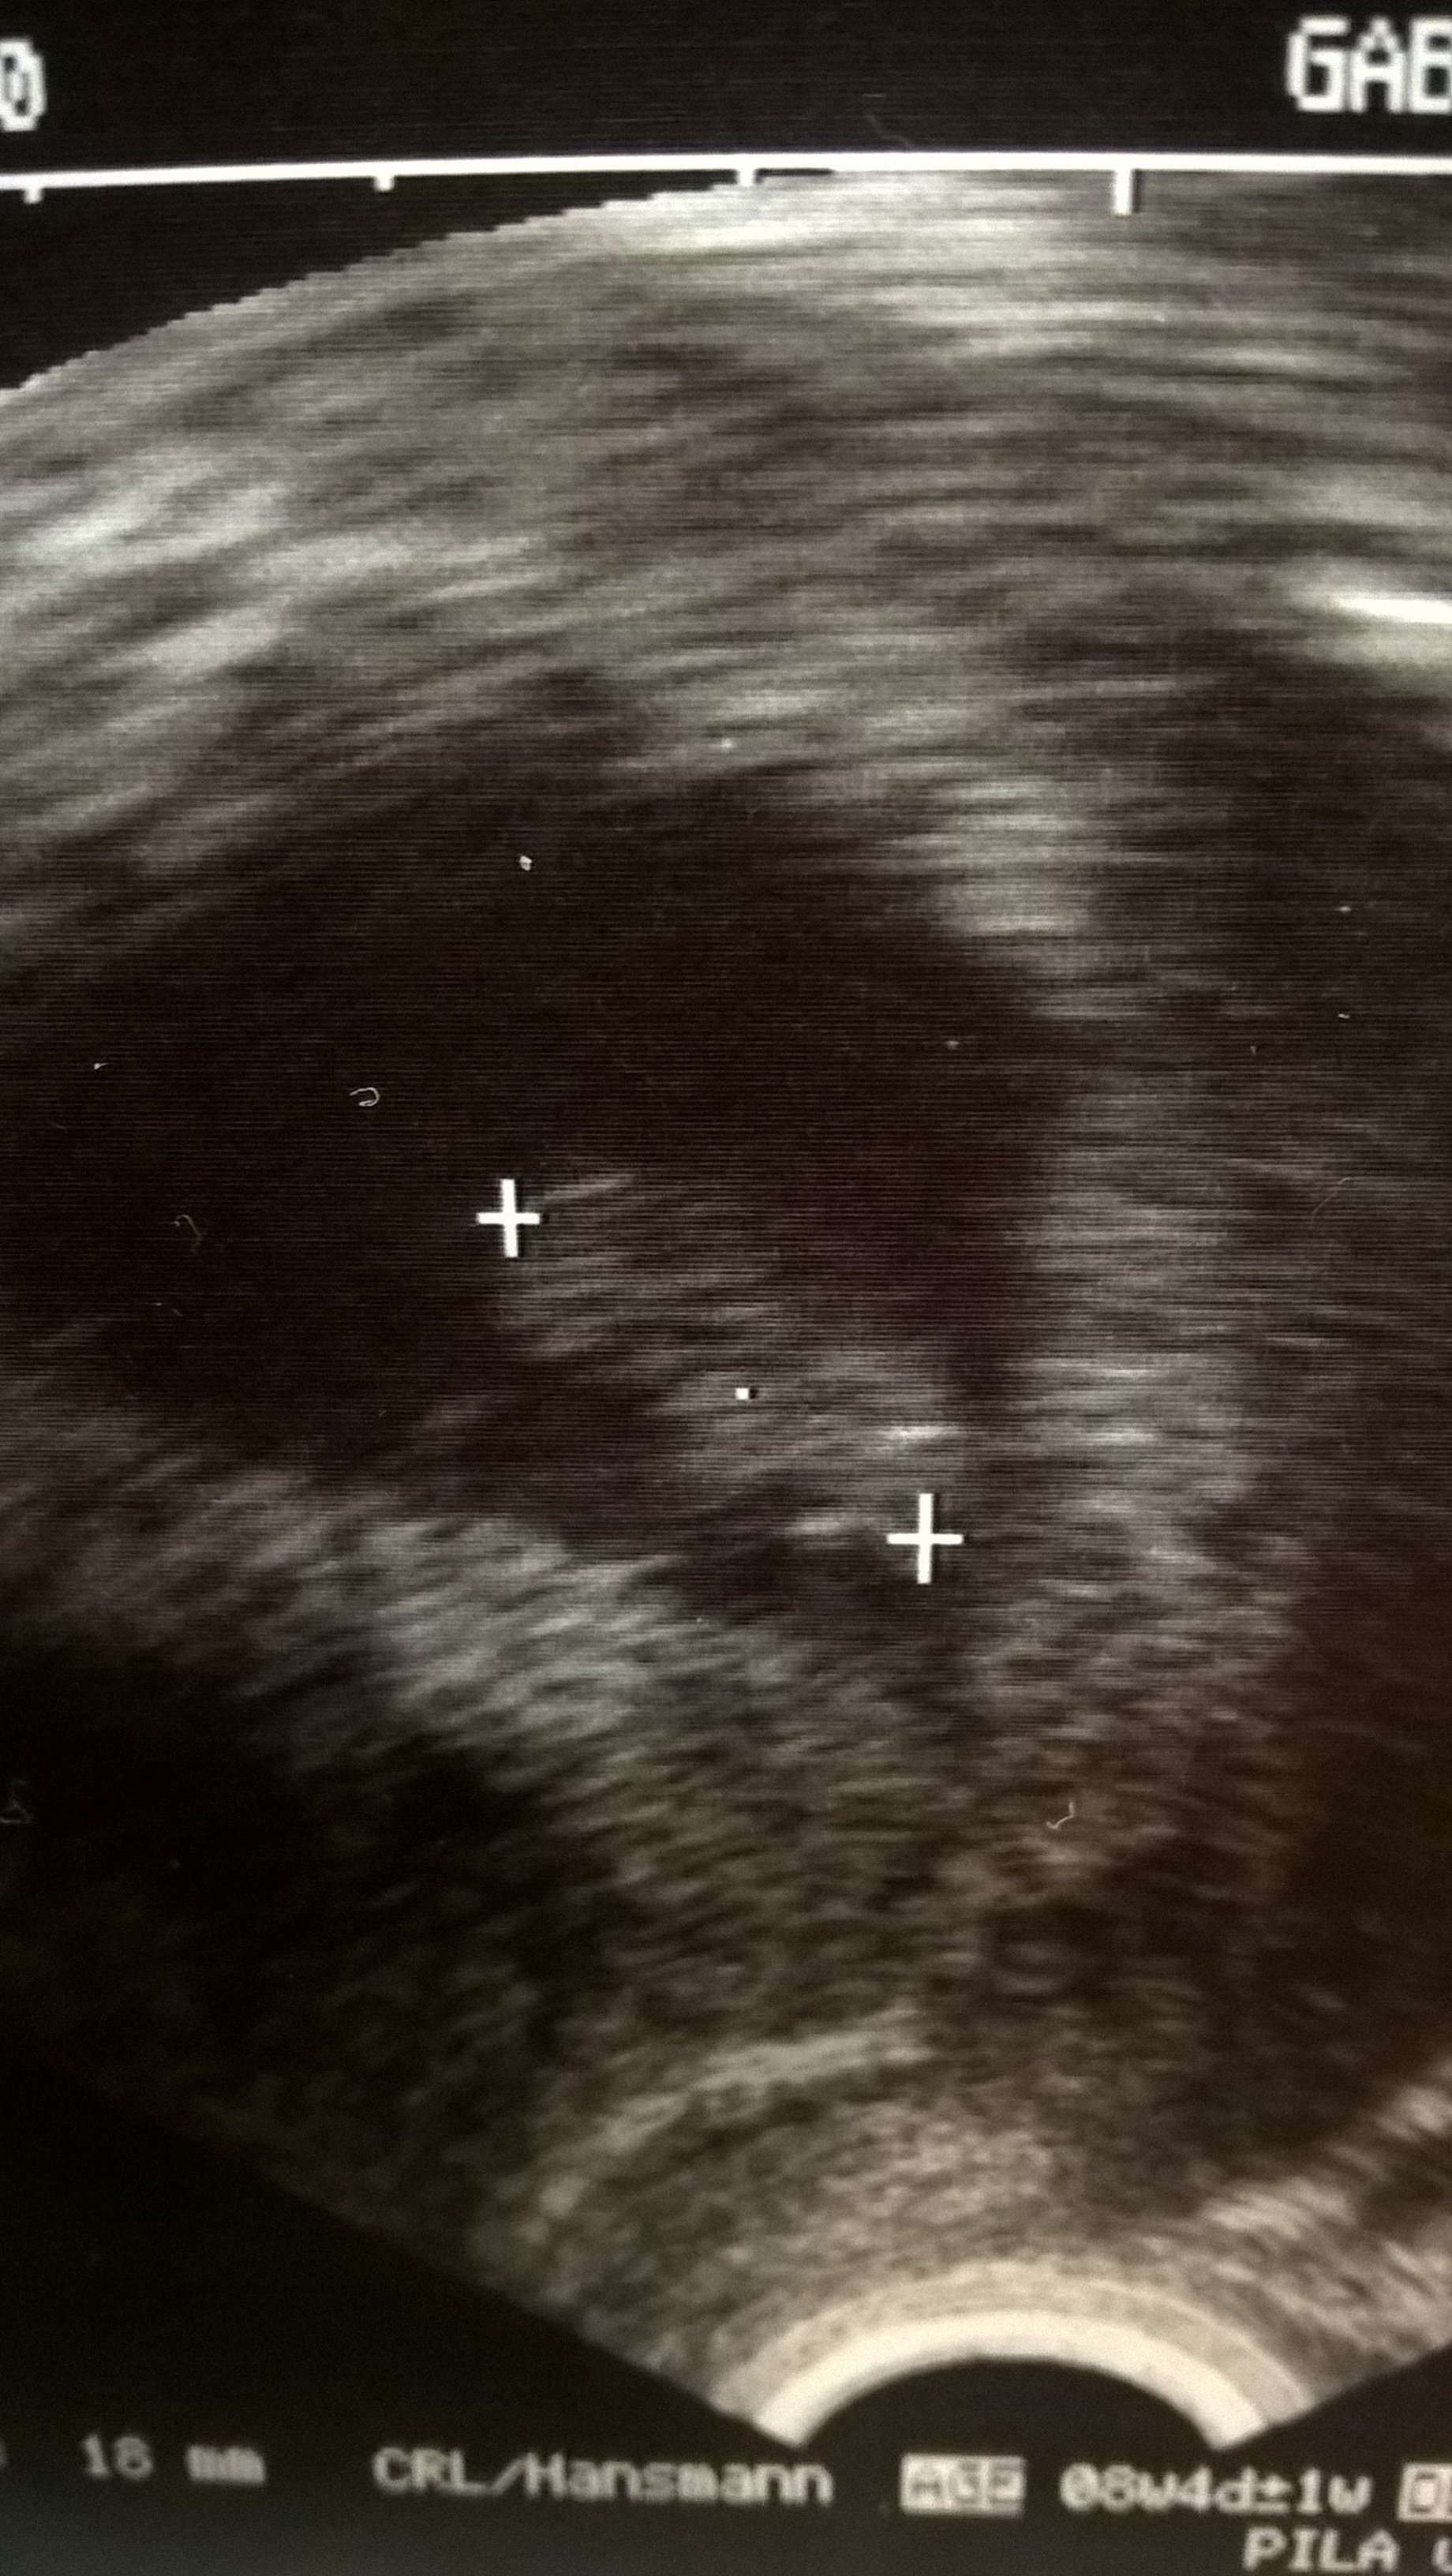

Moje Malutkie w 6t5d tez miało 7,6mm, także malusie, teraz nie wiem....dopiero 16go mam wizytę bo przesunęłam z 23go :) ale myślę, że jest ok :)